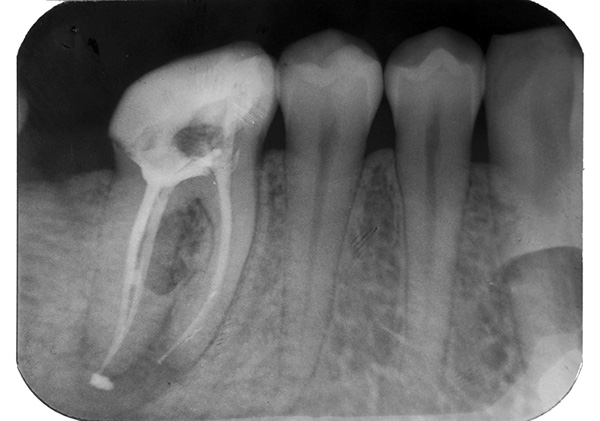

A saída do material de enchimento para o topo da raiz do dente

Um material moderno e amplamente utilizado para o preenchimento de canais são os pinos de guta-percha. Eles correspondem à marcação dos arquivos com os quais o canal é preparado e ajustam-se ao comprimento da raiz, não atingindo completamente a abertura anatômica da saída no tecido subjacente.

Outra variante do material de enchimento são vários cimentos em pasta, que endurecem dentro do canal dentário após um curto período de tempo.

Na odontologia, são utilizados materiais bioinertes, ou seja, pressupõe-se que sejam inofensivos ao organismo. No entanto, se o material de enchimento for retirado da raiz, poderá causar inflamação dos tecidos circundantes - como uma lasca no dedo.

Com a remoção excessiva do material de enchimento para o ápice, as dores pós-enchimento podem ser muito longas. Às vezes, a dor com pressão no dente pode persistir por meses.

Nesses casos, o dente deve ser tratado, porque, se o erro não for corrigido, o problema poderá não desaparecer completamente em seis meses (além disso, um cisto pode se formar na raiz).